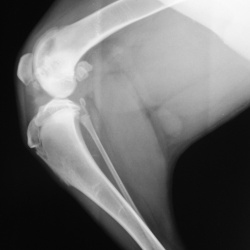

Собачка хромает третий месяц. А. Виктора Григорьевича Стовбы не видно…Что посоветуете уважаемые коллеги?